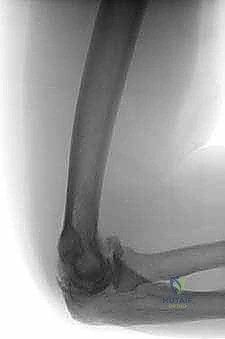

- التصوير بالأشعة السينية (X-rays): الفحص الأساسي الذي يُظهر تضيق المسافة المفصلية (دليل على تآكل الغضروف)، ووجود النتوءات العظمية، والأجسام السائبة الكبيرة.

- الأشعة المقطعية ثلاثية الأبعاد (3D CT Scan): أداة حاسمة ومفضلة لدى د. هطيف قبل أي تدخل جراحي. توفر الأشعة المقطعية خريطة ثلاثية الأبعاد دقيقة لموقع وحجم النتوءات العظمية والأجسام السائبة، مما يساعد في التخطيط الجراحي المسبق لضمان إزالتها بالكامل أثناء التنظير.